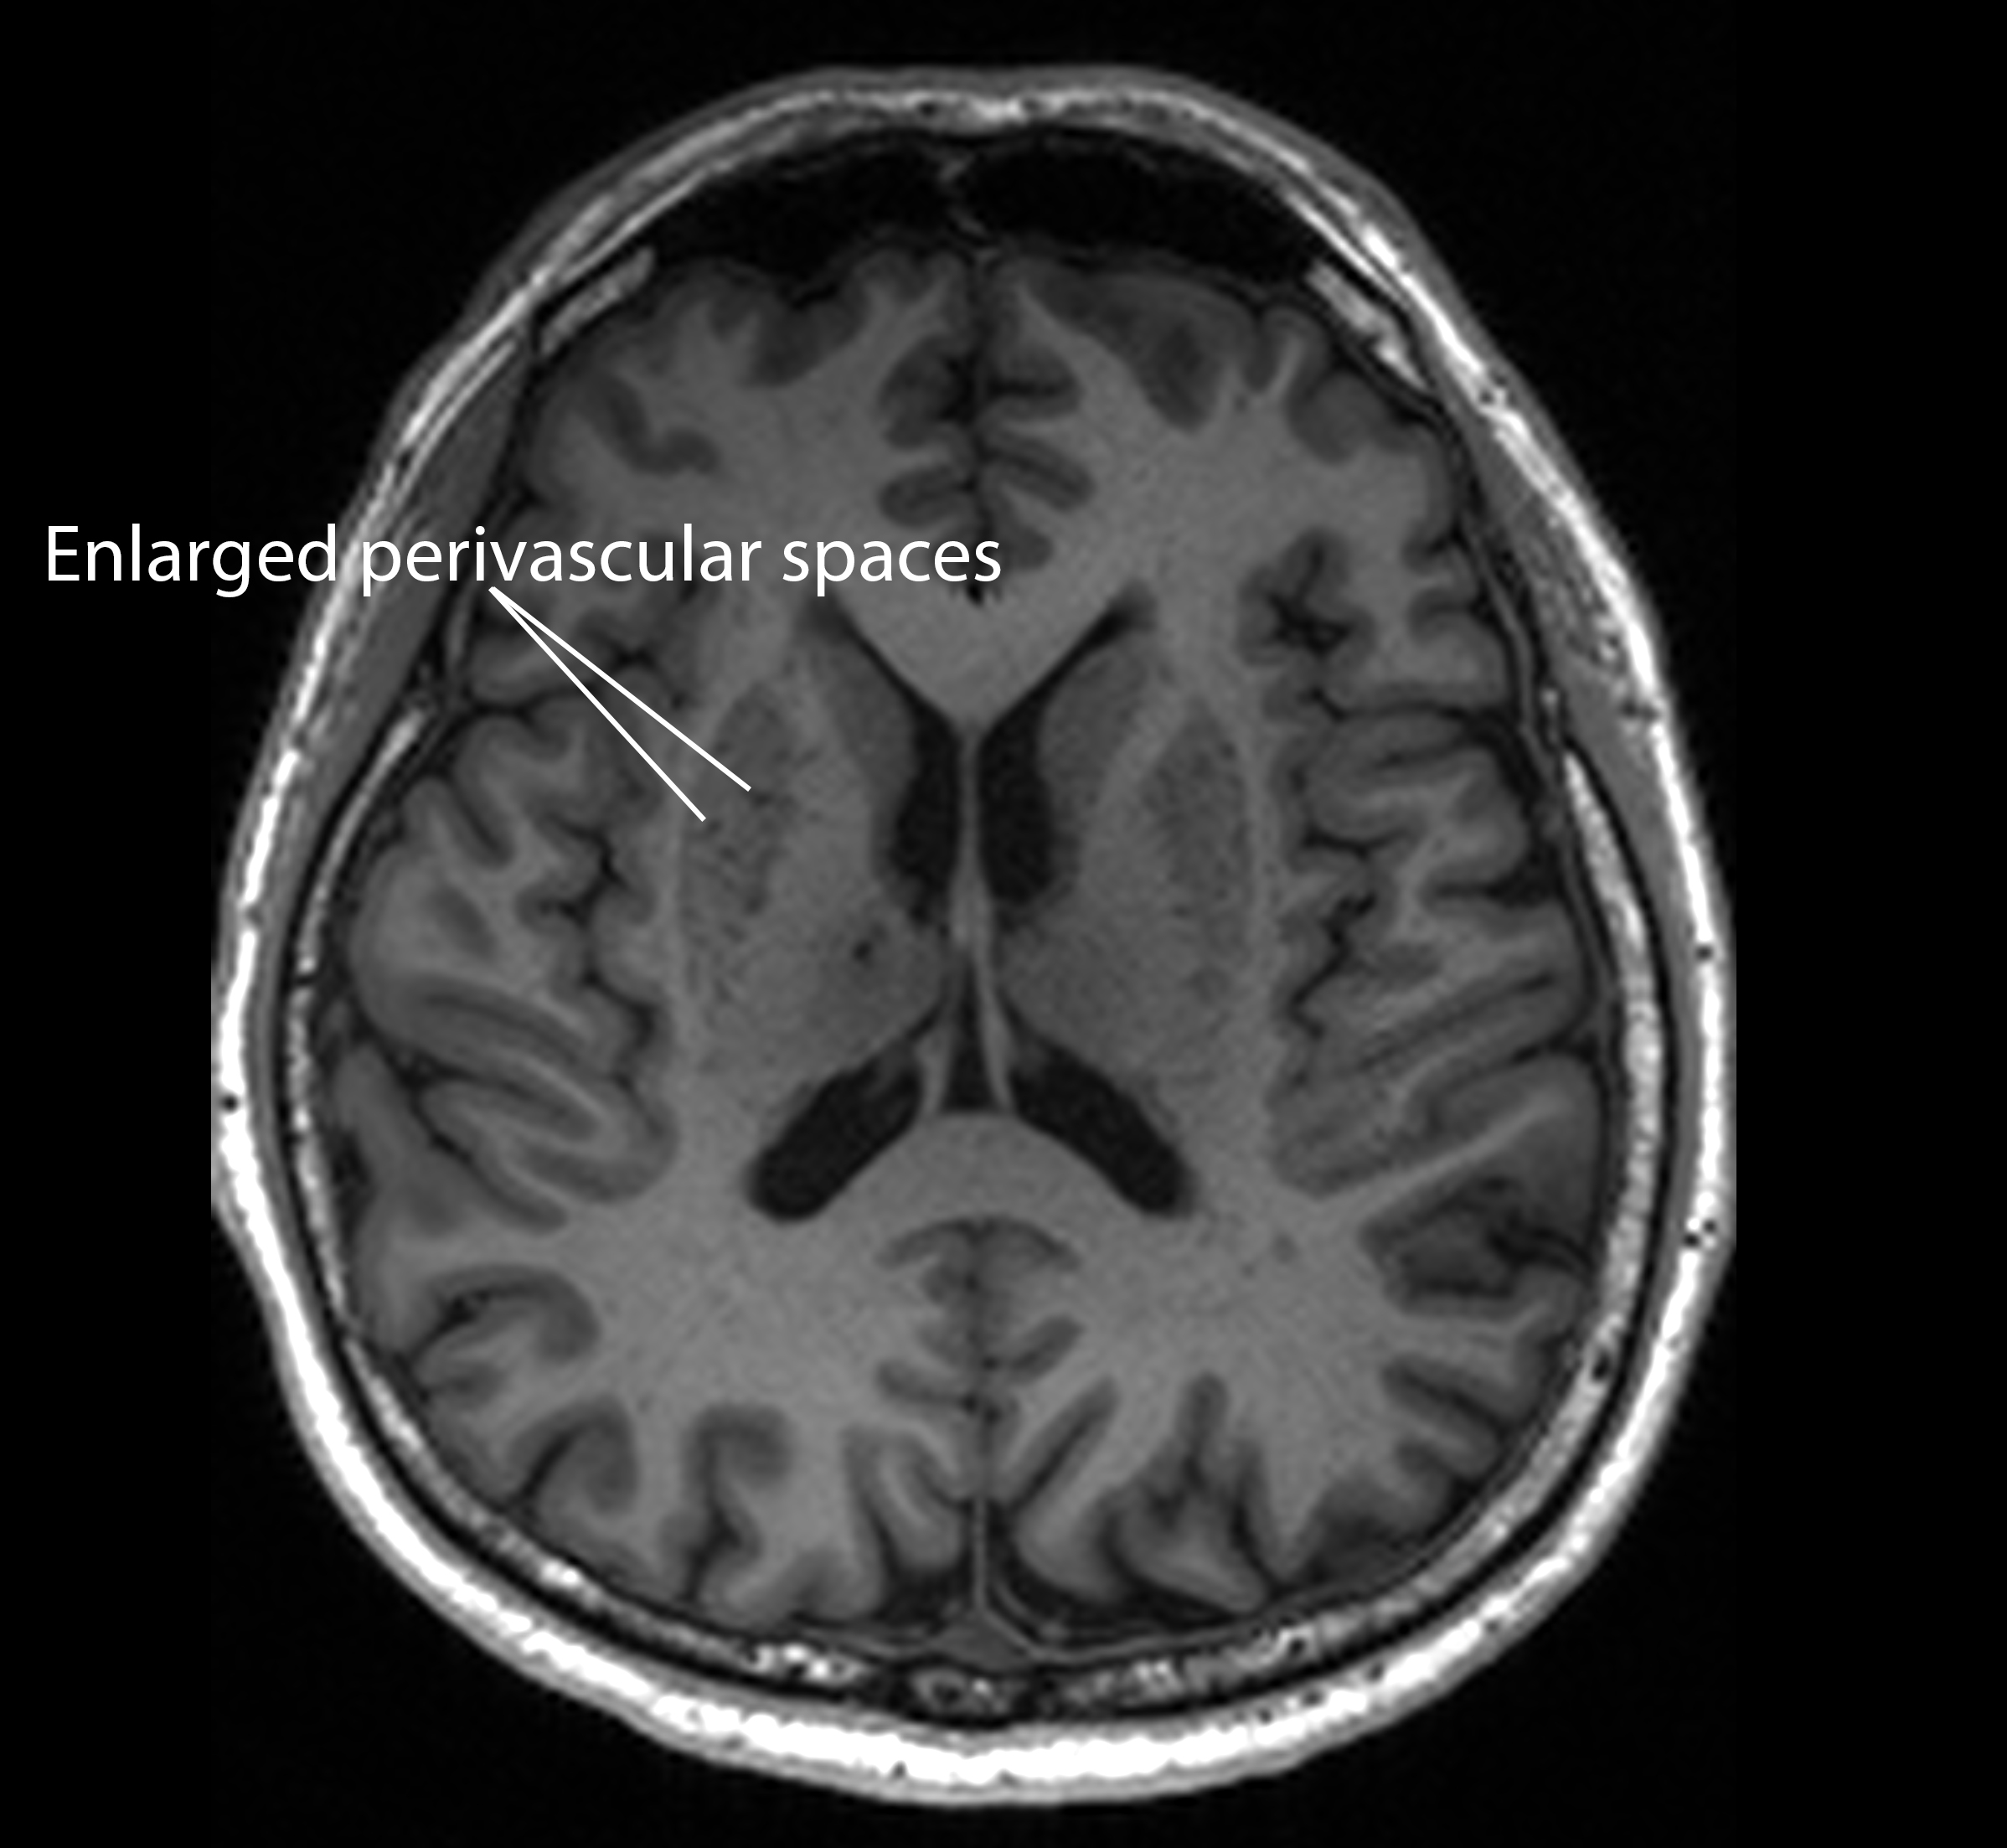

This suggests that such clogged drains, a condition known as “enlarged perivascular spaces”, are a likely early-warning sign for Alzheimer’s, a common form of dementia.

“Since these brain anomalies can be visually identified on routine magnetic resonance imaging (MRI) scans performed to evaluate cognitive decline, identifying them could complement existing methods to detect Alzheimer’s earlier, without having to do and pay for additional tests,” said DRCS Director Associate Professor Nagaendran Kandiah, the study’s senior author.

They found that those with mild cognitive impairment tend to have clogged drains in their brains, or enlarged perivascular spaces, compared to the other participants.

Additionally, the presence of clogged drains in the brain was linked to four of the seven biochemical measurements. So, people with enlarged perivascular spaces are likely to have more amyloid plaques, tau tangles and brain cell damage in their brains than normal, and thus at higher risk of developing Alzheimer’s disease.

Taking the study further, Justin compared white matter damage against enlarged perivascular spaces, and discovered that in participants with mild cognitive impairment, the link with biochemicals tied to Alzheimer’s was stronger for enlarged perivascular spaces than white matter damage. This suggests that choked brain drains are early indicators of Alzheimer’s disease.